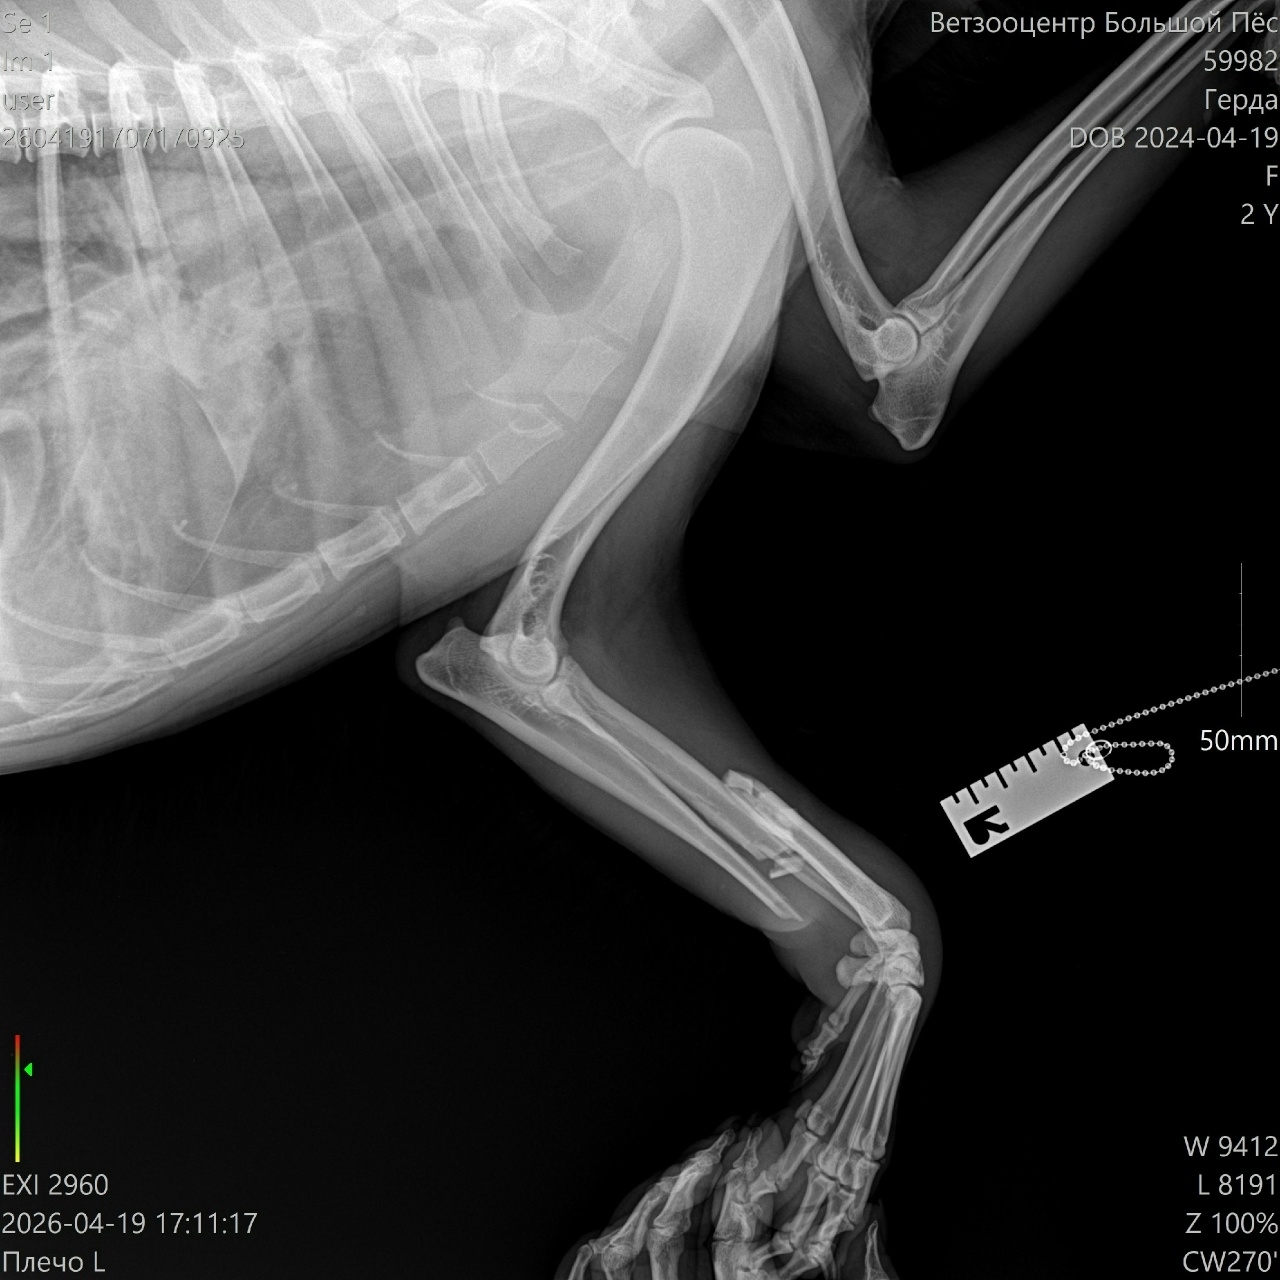

19 апреля была найдена сбитая собака в ошейнике с именем Римма, больше никакой информации. Ей сделали рентген - сложный перелом передней лапы. Собака крупная, 30кг. Находится временно в одном из СНТ. На посты о ней никто не откликнулся, хозяевам она видимо не нужна.

Собаку готовы принять в клинике "Ксоло" 23 апреля доктор Панков, либо в клинике "Юна", но нужны предварительно анализы, которых нет. По стоимости операция 50000 плюс стационар от 3500 до 6000 в сутки. Человек, приютивший на время собаку не располагает возможностями по ее содержанию и оплате. Есть возможность только привезти ее в Москву в клинику.